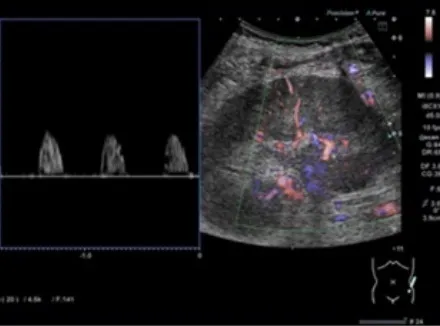

Na investigação de quadro de lesões de pele e calcificação extra-esquelética, observou-se um tumor calcificado no átrio esquerdo, bem como lesões ateroscleróticas calcificadas na aorta, artérias ilíacas e femorais, além de depósitos de cálcio no tecido subcutâneo e lesões na pele (figura abaixo).